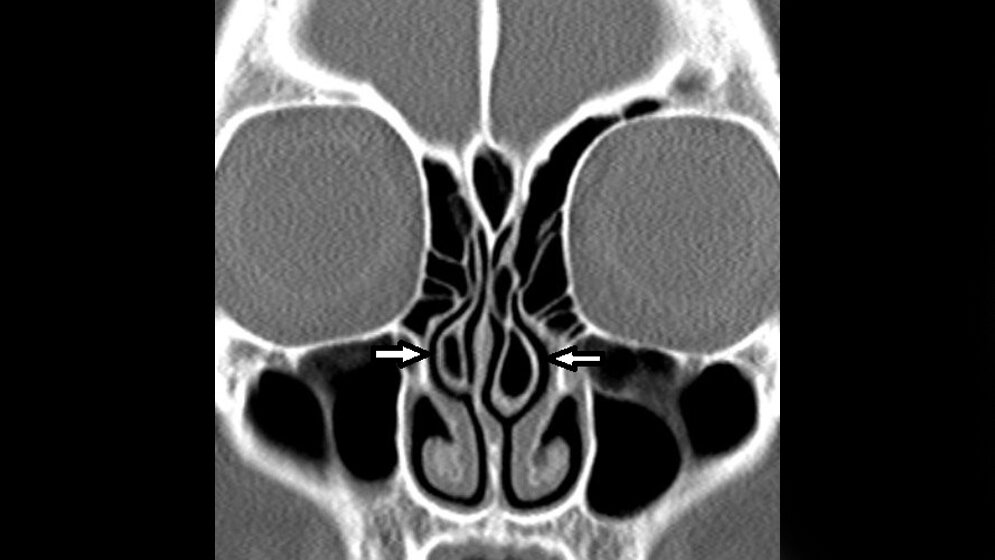

Skelettale Veränderungen 3.10: Concha bullosa

Die Concha bullosa ist eine häufig vorkommende anatomische Variante. Es gibt keine gesicherte Beziehung zwischen Concha bullosa und Sinusitis. Eine Nasenseptumdeviation kann indirekt Folge einer Concha bullosa sein. Eine erhöhte Inzidenz von Erkrankungen der paranasalen Sinus im Zusammenhang mit einer Concha bullosa besteht nicht.

Concha bullosa is a common anatomical variation. There is no relationship between size and sinusitis. Nasal septum deviation can be an indirect result of the presence of concha bullosa. No in-creased incidence of paranasal sinus disease exists in patients with concha bullosa.